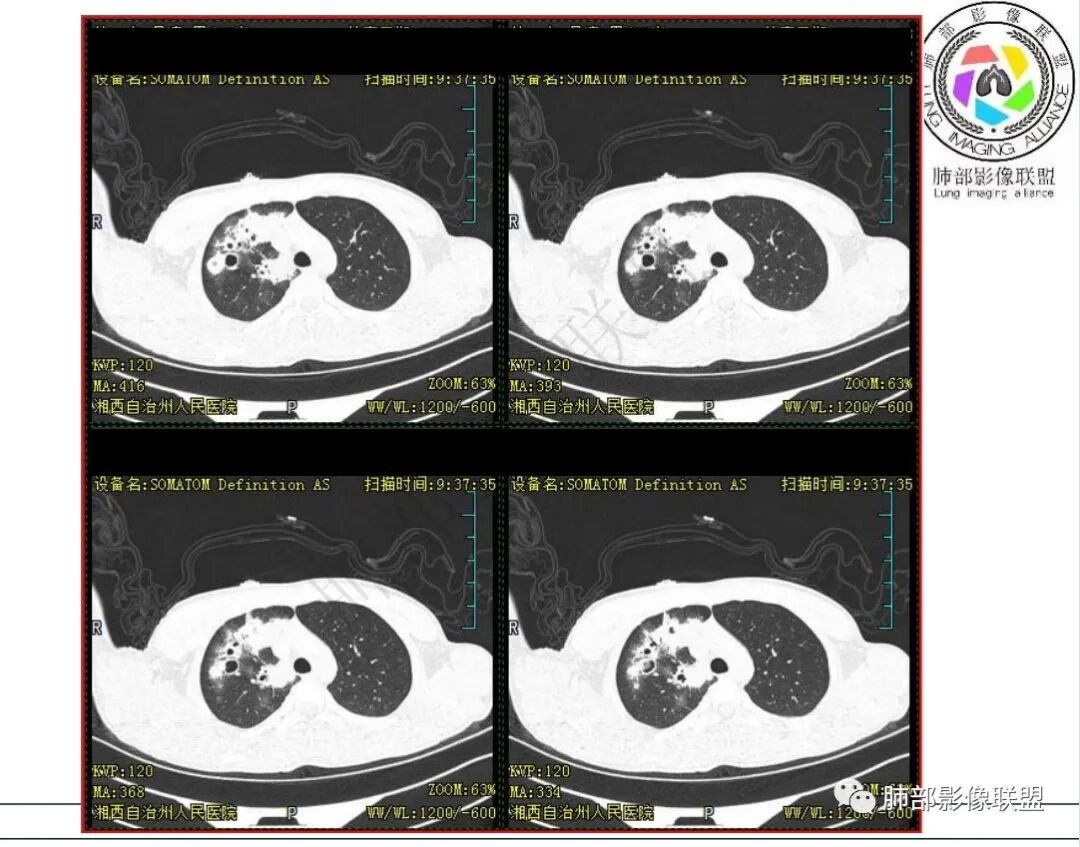

影像:右肺上叶多发实变影结节影,边界模糊,边缘收缩,伴多发空洞,洞壁光滑,部分支气管壁增厚。

右肺上叶体积略缩小,大片状实变区,内有空洞影,内壁光滑,张力偏高,实变区内见充气支气管,病变周围多发片状磨玻璃影,界不清,多次送检未检测到结核杆菌,儿童,咳嗽,咳痰,咳血病史,考虑NTM

男,15岁,咳嗽咳痰伴咯血盗汗10余天。既往有结核病患接触史。血沉增高,淋巴细胞稍低。胸部CT:右肺上叶多发实性斑片影、结节影、索条影,边界模糊,周围晕,边缘收缩,部分病灶内空洞,洞壁光滑。感觉病灶与血管关系密切。考虑:多发,多形态,空洞,血管炎?WG?鉴别TB、NTM、奴卡等慢性感染。

3.首次CT提示:右肺上叶多发结节影及实变影,簇状分布,周围散在磨玻璃影,结节内多类圆形空洞,内壁光整,有一定张力,偶见液平。部分支气管壁增厚。

考虑良性感染性病变可能。

4.患者年龄、临床与影像都会首先考虑结核,但是结核相关各项实验室检查均阴性,没有找到病原学依据。

因此,还应当排除NTM,影像可以酷似结核灶。

5.抛开分布不谈 其他的,临床中毒症状不明显、非易感人群,肺结节、实变、晕征、空洞等等都可以符合隐球感染。

本例病灶分布特点比较偏中央分布,不是我们常见的隐球外围胸膜下。看来诊断隐球,分布不能太绝对,至少不能作为绝对排除项。